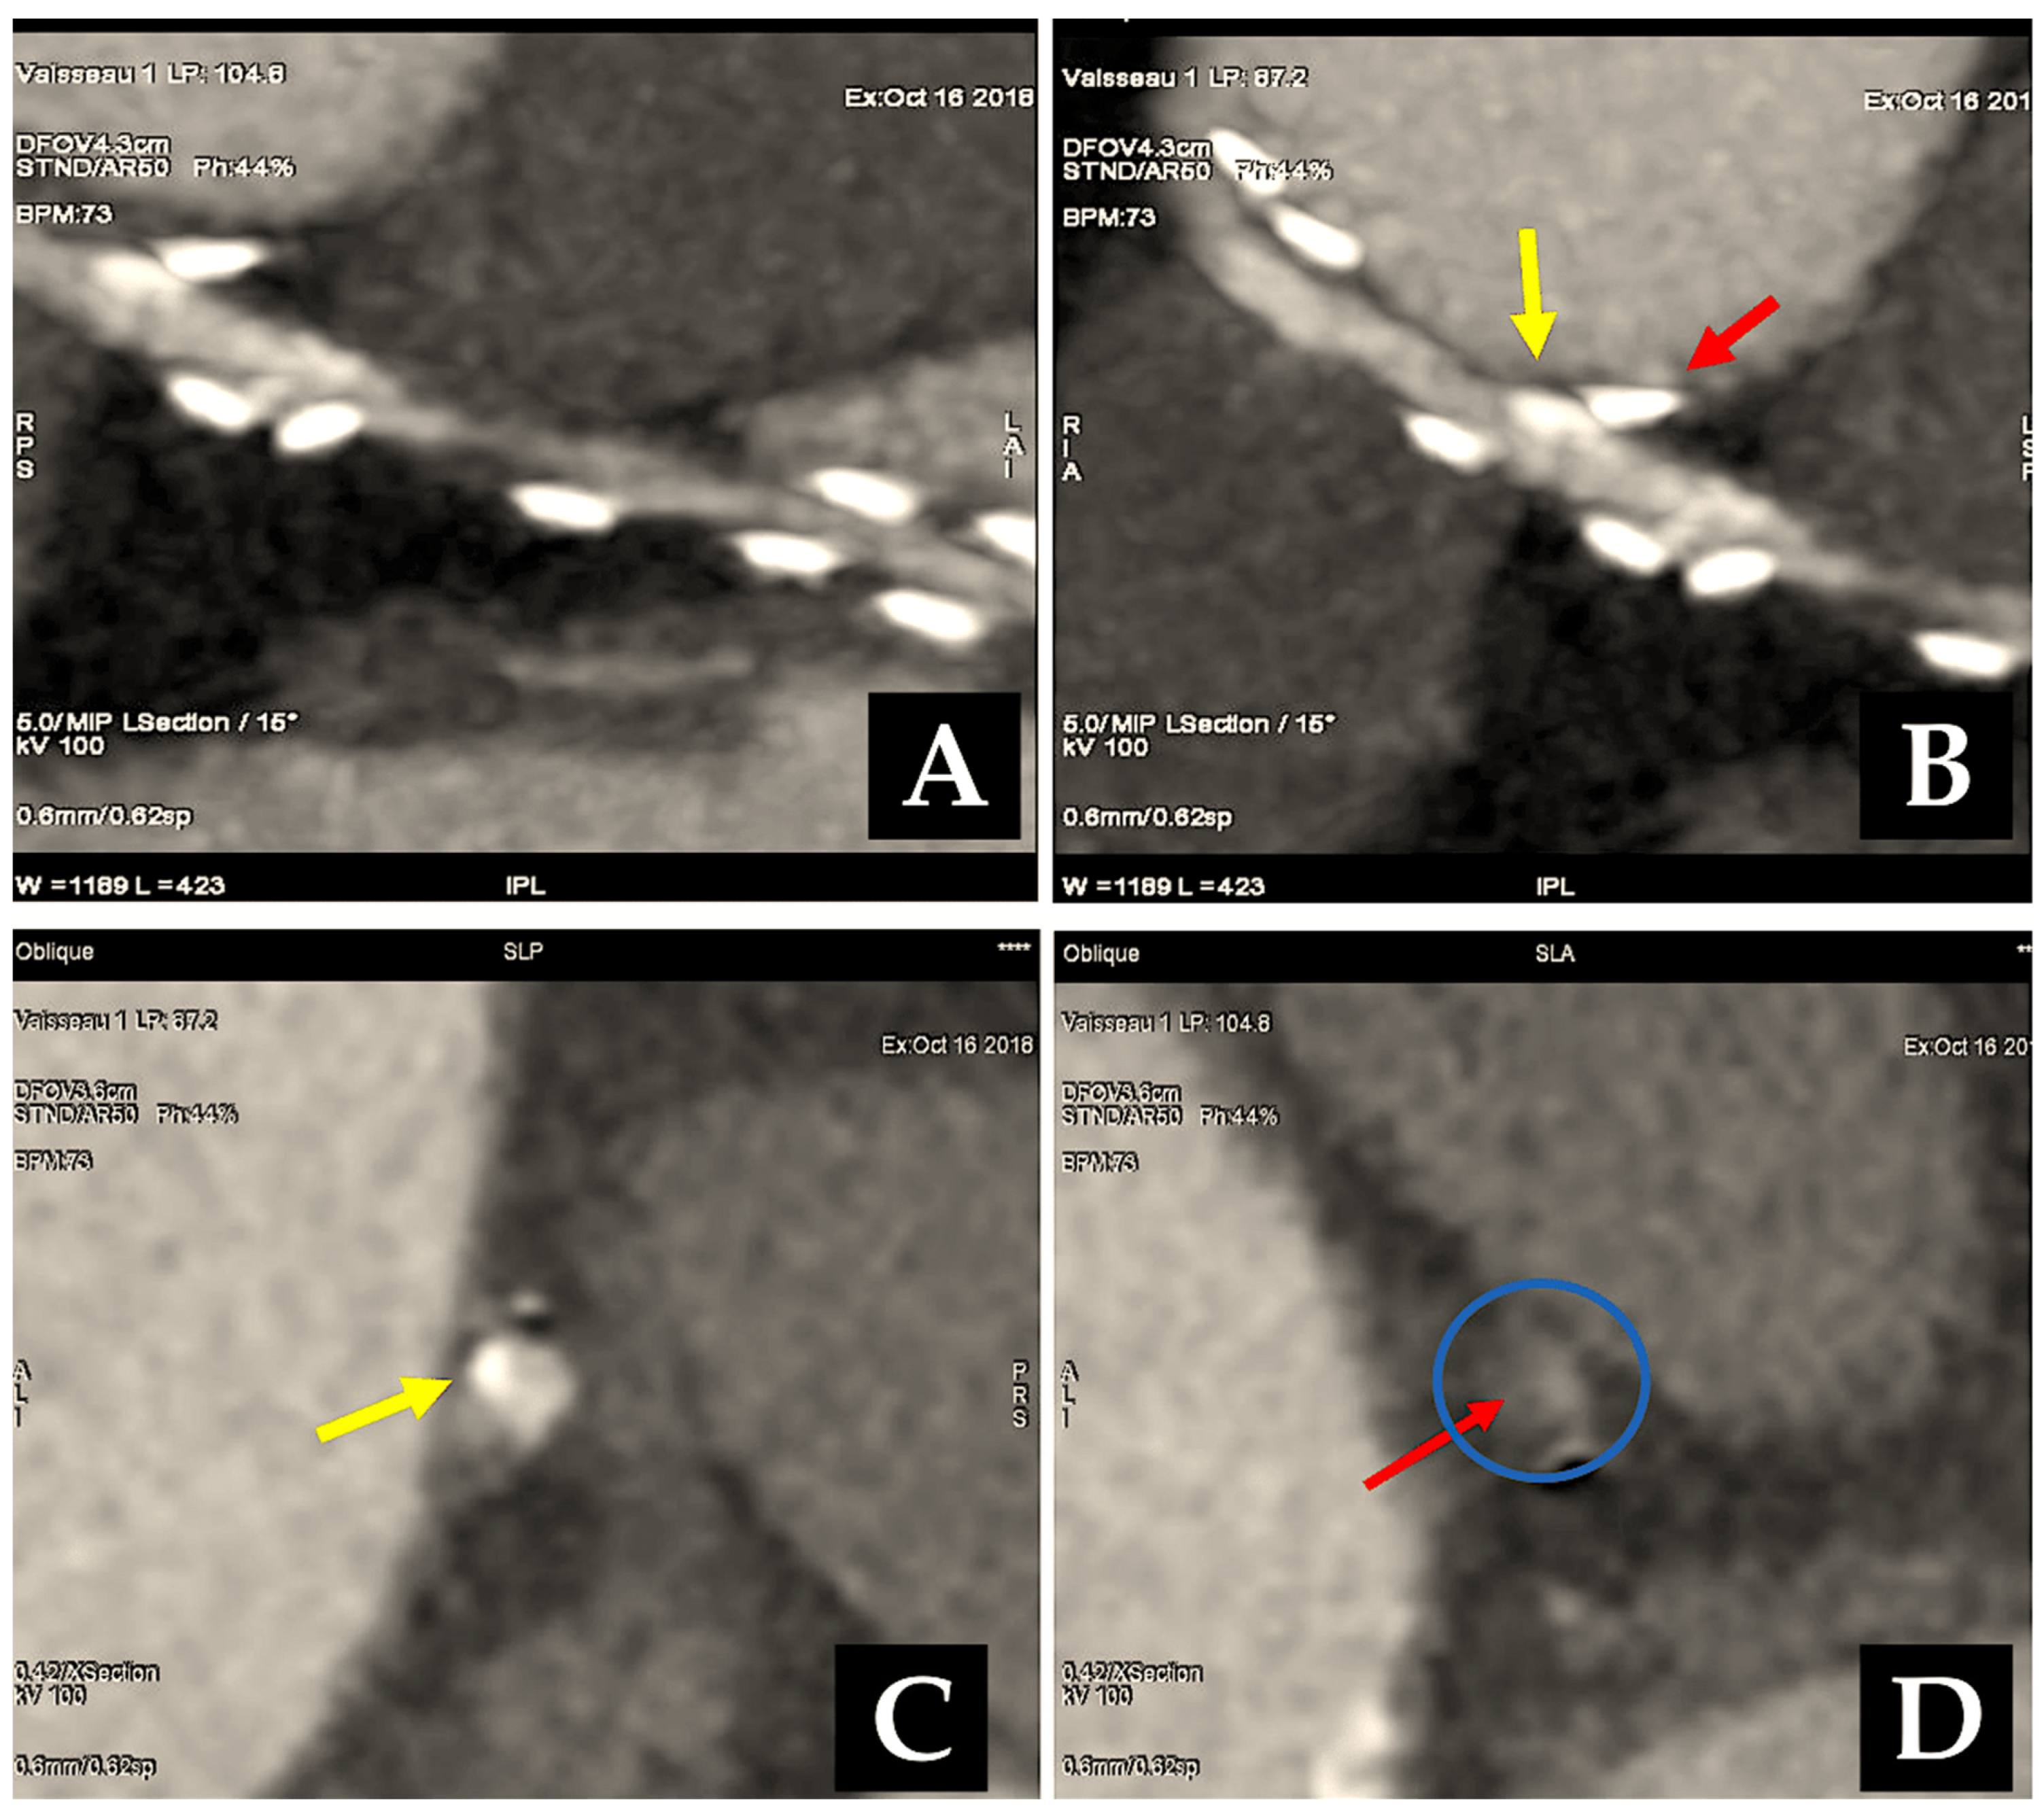

Two distinct meta-analyses have corroborated this conclusion over the past two years, not only in larger cohorts of patients but also with longer-term follow-up. A single study encompassed 27 observational reports comprising a total of 79,000 patients, comprising approximately one-quarter of those with BITA. The findings indicated a statistically significant reduction in long-term mortality rates with BITA (p < 0.00001) [189]. An investigation conducted by Yi and Associates [190] included nine observational series of over 15,000 patients, representing approximately half of whom had BITA, with follow-up lasting a mean period of nine years. The analysis revealed a notable decline in fatality rates associated with BITA (HR: 0.79; 95% CI: 0.75 to 0.84). It is noteworthy that no study has documented any adverse impact of BITA on the fatality rate (Figure 7).

Figure 7.

CABG has been performed using best isolated technically appropriate anastomosis, either as an isolated termino-lateral graft with pediculate ITA or in a Y-shaped configuration with sequential BITA grafts. Controls have been achieved through the utilisation of computed tomography angiography. (A–F): The post-processing of computed tomography angiography of CABG was conducted using volume rendering and two-dimensional curved imaging with automatic tracking. (A–C): Illustrations of the utilisation of two-dimensional curved imaging in conjunction with automatic tracking in the context of CABG. (A): LITA has been anastomosed to the LAD. (B): LITA sequential grafting on LAD and the first diagonal branch. (C): RITA anastomosed on the first obtuse branch. (D–F): Volume rendering imaging of CABG. (D): 1. LITA, 2. LITA on the diagonal branch, and 3. LITA-LAD. (E,F): Illustrations of the grafting of the RITA on the CCA. The white arrow (1) indicates the course of the RITA between the aorta and the left atrium. (2) This image depicts distal grafting on the first obtuse branch. Abbreviations: CABG, coronary artery bypass grafting; CCA, circumflex coronary artery; LITA, left internal thoracic artery; LAA, left atrial appendance; LAD, left anterior descending artery; RCA, right coronary artery; RITA, right internal artery.